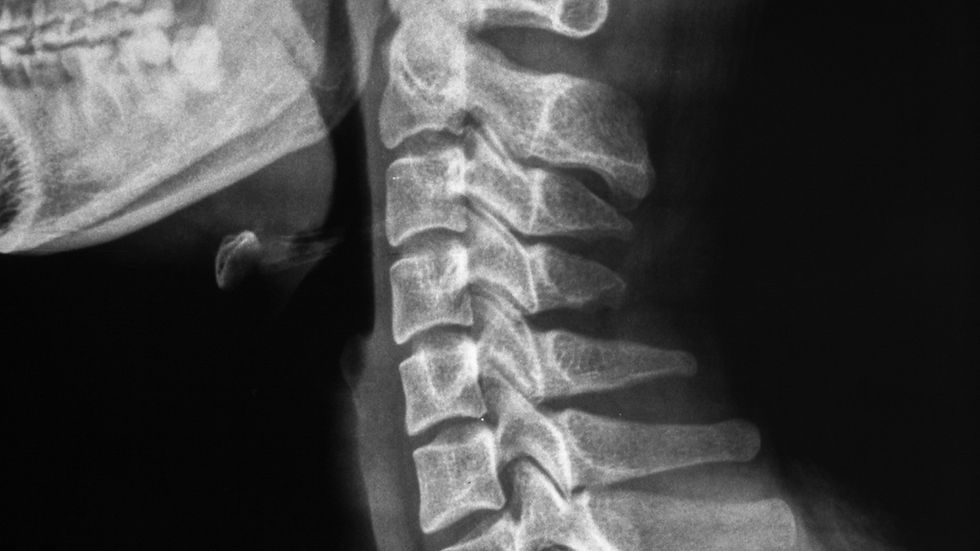

Cuando se trata de cuidar la columna, no todo se limita a observar cómo te mueves o a escuchar lo que sientes. Hoy en día, también es posible medir cómo está funcionando tu cuerpo mediante estudios especializados que aportan información objetiva y útil para el cuidado quiropráctico.

La miografía superficial es un estudio rápido y no invasivo que permite evaluar los patrones de actividad muscular y la forma en que el sistema neuromuscular responde en diferentes áreas de la columna.